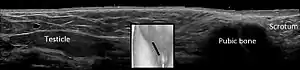

| Cryptorchidism on scrotal ultrasound | |

In the minority of cases with bilaterally nonpalpable testes, further testing to locate the testes, assess their function, and exclude additional problems is often useful. Scrotal ultrasound or magnetic resonance imaging performed and interpreted by a radiologist can often locate the testes while confirming absence of a uterus. At ultrasound, the undescended testis usually appears small, less echogenic than the contralateral normal testis and usually located in the inguinal region. With color Doppler ultrasonography, the vascularity of the undescended testis is poor.